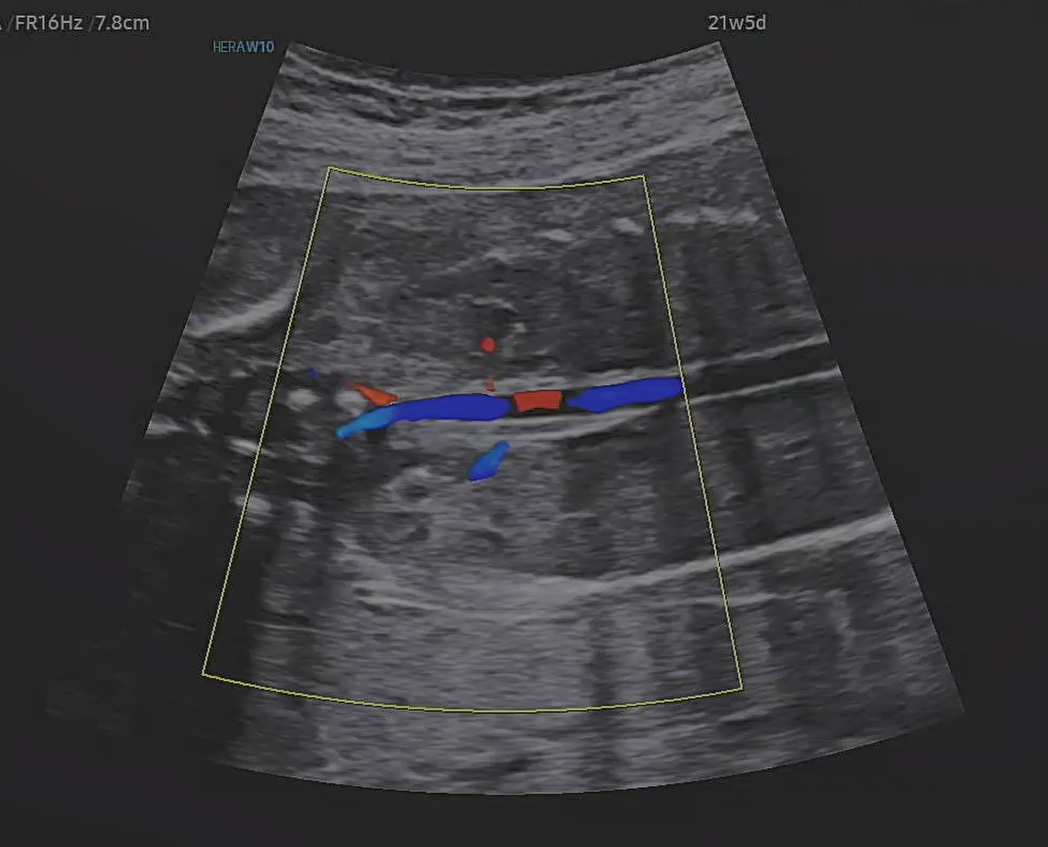

정밀 초음파 검사

21주 5일, 정밀 초음파 검사가 있는날이었다.

정밀 초음파는 기관들이 잘 형성되어 있는지 초음파로 확인 하는 것이라고 했다.

신장?으로 들어가는 혈류라고 하셨던것 같다.

이런것까지 보이는게 정말 신기했다.

초음파 진단 기술이 정말 많이 발전 한것 같았다.

어떻게 태아 혈류까지 이렇게 잘 보이는지 원